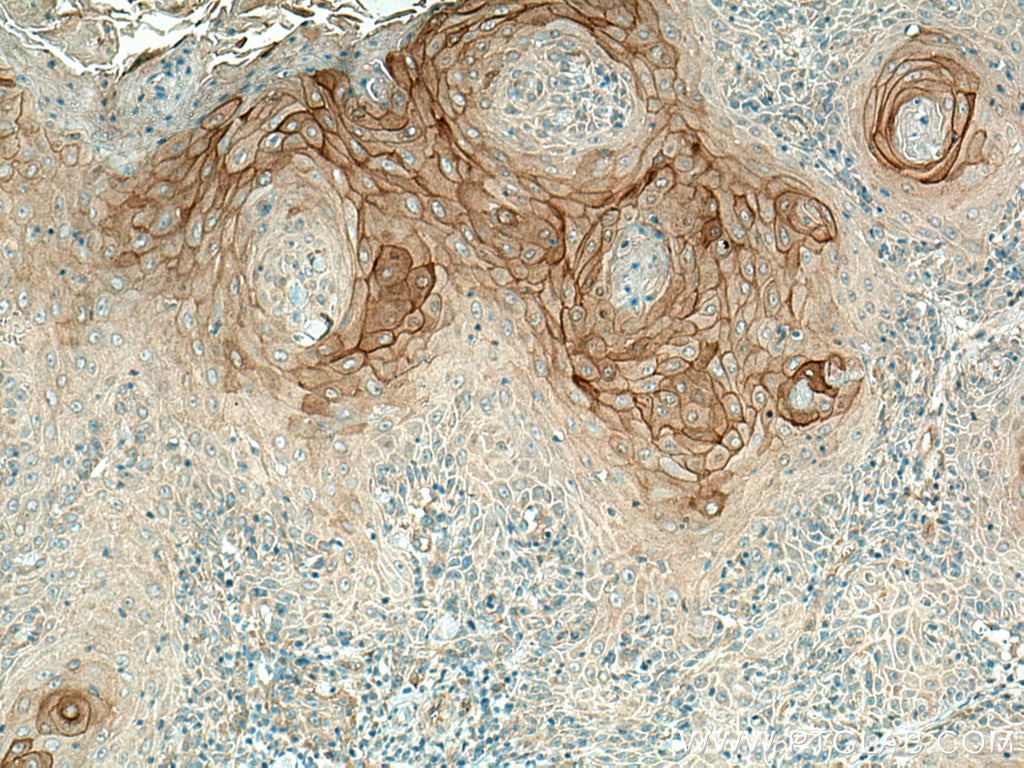

| Positive IHC detected in | human skin cancer tissue, human colon cancer tissue Note: suggested antigen retrieval with TE buffer pH 9.0; (*) Alternatively, antigen retrieval may be performed with citrate buffer pH 6.0 |

| Immunohistochemistry (IHC) | IHC : 1:200-1:800 |